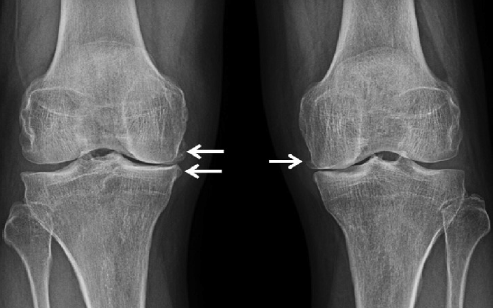

2

3

4